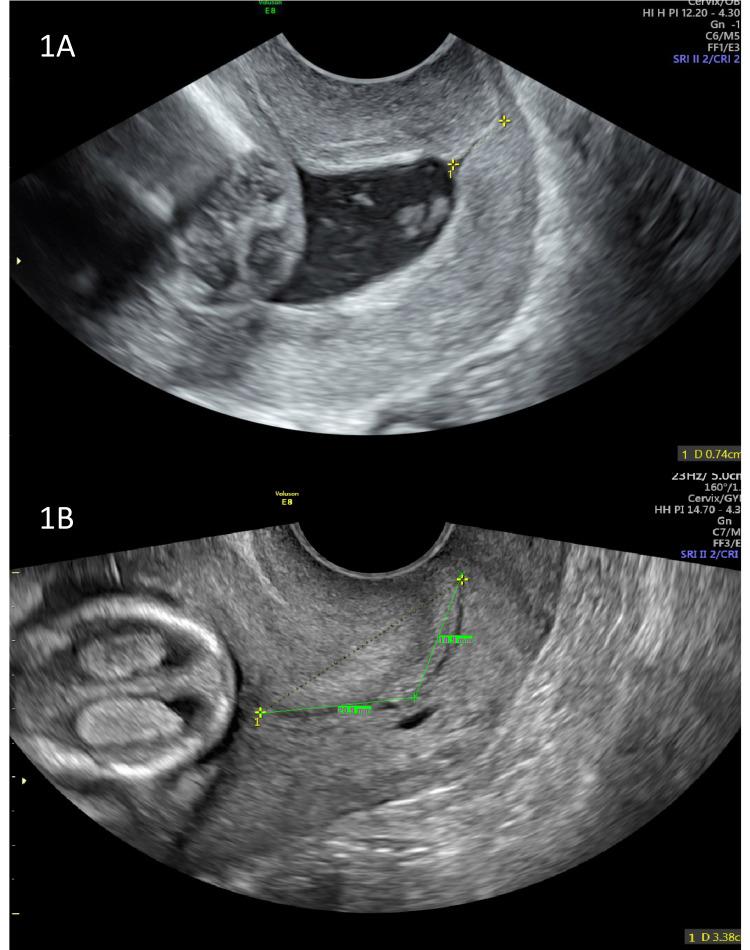

Preterm birth (PTB) affects approximately 10% of births globally each year and is the most significant direct cause of neonatal death and of long-term disability worldwide. Early identification of women at high risk of PTB is important, given the availability of evidence-based, effective screening modalities, which facilitate decision-making on preventative strategies, particularly transvaginal sonographic cervical length (CL) measurement. There is growing evidence that combining CL with quantitative fetal fibronectin (qfFN) and maternal risk factors in the extensively peer-reviewed and validated QUanititative Innovation in Predicting Preterm birth (QUiPP) application can aid both the triage of patients who present as emergencies with symptoms of preterm labor and high-risk asymptomatic women attending PTB surveillance clinics. The QUiPP app risk of delivery thus supports shared decision-making with patients on the need for increased outpatient surveillance, in-patient treatment for preterm labor or simply reassurance for those unlikely to deliver preterm. Effective triage of patients at preterm gestations is an obstetric clinical priority as correctly timed administration of antenatal corticosteroids will maximise their neonatal benefits. This review explores the predictive capacity of existing predictive tests for PTB in both singleton and multiple pregnancies, including the QUiPP app v.2. and discusses promising new research areas, which aim to predict PTB through cervical stiffness and elastography measurements, metabolomics, extracellular vesicles and artificial intelligence.

早产(PTB)每年影响全球约10%的分娩,是全球新生儿死亡和长期残疾的最重要直接原因。鉴于有循证有效的筛查方式,早期识别早产高危女性很重要,这些筛查方式有助于就预防策略做出决策,特别是经阴道超声测量宫颈长度(CL)。越来越多的证据表明,在经过广泛同行评审和验证的预测早产的定量创新(QUiPP)应用中,将宫颈长度与定量胎儿纤连蛋白(qfFN)和母体风险因素相结合,有助于对出现早产症状的急诊患者以及前往早产监测诊所的高危无症状女性进行分流。QUiPP应用程序的分娩风险因此支持与患者就是否需要增加门诊监测、早产住院治疗或仅仅是让那些不太可能早产的患者放心进行共同决策。对早产患者进行有效的分流是产科临床的一个优先事项,因为正确适时地使用产前皮质类固醇将使新生儿受益最大化。本综述探讨了现有预测早产的检测方法在单胎和多胎妊娠中的预测能力,包括QUiPP应用程序v.2,并讨论了有前景的新研究领域,这些领域旨在通过宫颈硬度和弹性成像测量、代谢组学、细胞外囊泡和人工智能来预测早产。